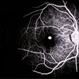

- Giant Retinal Tear

- giant retinal tear, idiopathic

- Fundus photograph of a 40-year-old man who presented with a history of progressive inferior visual field defect in the right eye over 2-3 weeks.